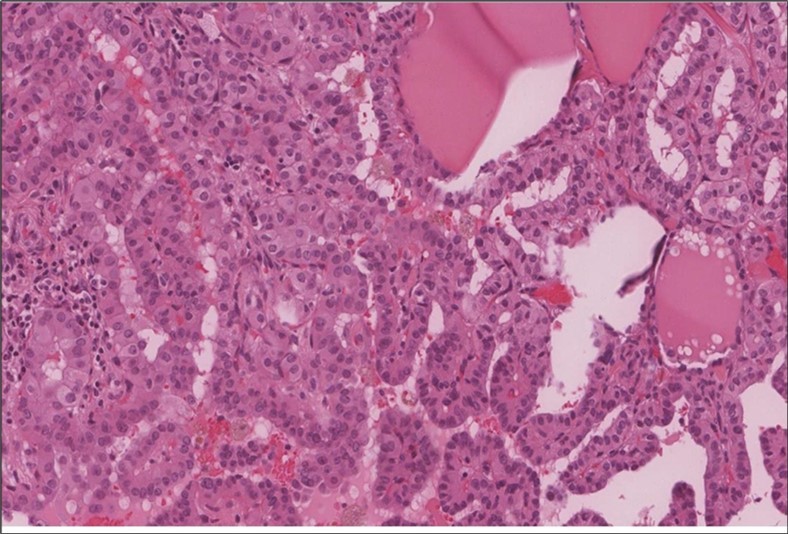

When diagnosing thyroid swelling, imaging studies have been helpful in differentiating malignant from benign tumors with US being used as an initial evaluation tool when assessing thyroid nodules. Tumors are categorized based on composition, echogenicity, shape, margin and echogenic foci into added scores determined by the TI-RADS system, which determines the need for FNA 13. Other imaging modalities include MRI and CT. However; radiological assessment does not distinguish between the types of thyroid cancer, and therefore FNA and biopsy are of crucial importance 3, 6. On a pathologic sample, LMS appears as spindled eosinophilic cells with elongated blunt-ended or cigar-like nuclei arranged in fascicles 2, 7 (Figure 1, Figure 2, Figure 3). Despite the unique microscopic morphology, LMS cannot be distinguished from other spindle cell tumors such as spindle cell variant of medullary thyroid cancer, anaplastic thyroid

Figure 3.Left thyroid The malignant looking cells are showing diffuse atypia, mitosis and hyper-chromatic nuclei, some remaining follicles could be noted as well (H&E, ×400).

cancer, or other metastatic tumors without further testing with genetic or molecular studies 3, 7. Immunohistochemical testing plays a vital role in differentiating LMS from such similar tumors as it stains positive for vimentin and smooth muscle actin (SMA), and is variably positive for HHF35, desmin (50%-100%), and H-caldesmon 3, 6. Moreover, there were no reported cases where thyroid LMS stained positive for thyroglobulin, cytokeratin, calcitonin, chromogranin, or protein S100 3. Our patient’s left thyroid biopsy showed the characteristic microscopic features and was positive for SMA, desmin, caldesmon, P63 with patchy EMA (Figure 1, Figure 2, Figure 3, Figure 4) as well as her liver biopsy (Figure 5, Figure 6, Figure 7); whereas her right thyroid showed clear papillary thyroid cancer cell features (Figure 8, Figure 9).